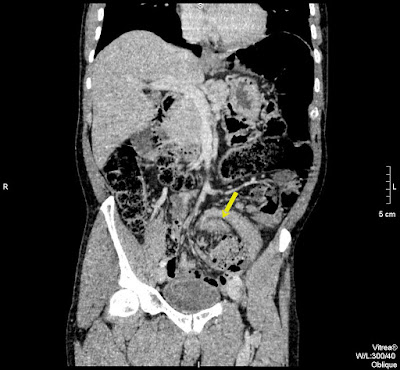

45 koruli ferfi. Elozmenyben hasi mutet nincsen. Ket napja puffad a beteg hasa, azota nincsen szeklet. A CRP minimalisan emelkedett, a FVS normalis. Laz nincsen, feszes, gazos has.

Vastagbel occlusio eseten vizsgalando:

– coecum a helyen van-e (volvulus coecalis eseten a bal hypochondriumban van)

– faecaloma

– ha a nativ hasi felvetelen kavebab-jel latszik, akkor sigma-volvulus

A zsirdenzitas a mesenterium „beforgasat” jelzi a belfal negyezte koze az organo-axialis formanak megfeleloen.

Azert nincs szep whirlpool sign = signe de tourbillone = orveny jel?, mert nem a mesenterium a forgastengely, hanem maga a sigma.